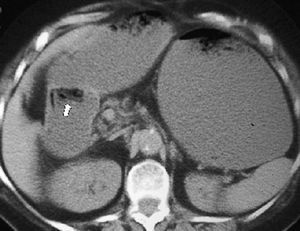

La lesión duodenal por traumatismo es rara y es la tercera porción del duodeno la que con más frecuencia se lesiona al ser comprimida contra la columna. Se puede producir contusión o perforación, observándose en ambas situaciones engrosamiento de la pared duodenal, borrosidad de la grasa periduodenal o líquido en el espacio pararrenal anterior derecho. En caso de contusión se puede identificar el hematoma como una colección de densidad intermedia o alta que comprime la luz duodenal en la TC. Signos de perforación son la presencia de aire adyacente al duodeno retroperitoneal (fig. 3) o la extravasación de contraste oral al retroperitoneo9,10.

Fig. 3--Perforación duodenal traumática. Estudio de tomografía computarizada que muestra aire en retroperitoneo (flecha) tras traumatismo.